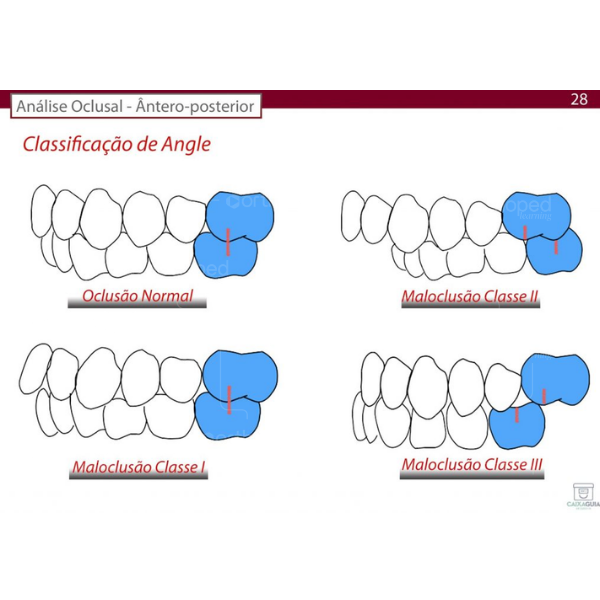

Antes de conversarmos sobre a atresia de maxila nos diferentes padrões de face, vamos entender que a relação de Classe I, Classe II e Classe III é uma relação dentária definida por Angle a partir da intercuspidação entre os primeiros molares permanentes e seu alinhamento.

A partir daí temos a Classificação de Angle baseado na relação molar, onde:

Oclusão normal – é definida pela Relação molar normal (Classe I) e dentes na linha de oclusão;

Má oclusão de Classe I – Relação molar normal (Classe I) e demais dentes mal posicionados (apinhados, girovertidos…);

Má oclusão de Classe II – Molar inferior DISTAL (para trás) em relação ao superior;Má oclusão de Classe III – Molar inferior MESIAL (para anterior) em relação ao superior.

Esta classificação foi sendo aprimorada para definir melhor os tipos de maloclusão, além de ser utilizada também como referência para relação entre as bases ósseas, ou seja, para a relação maxilomandibular.